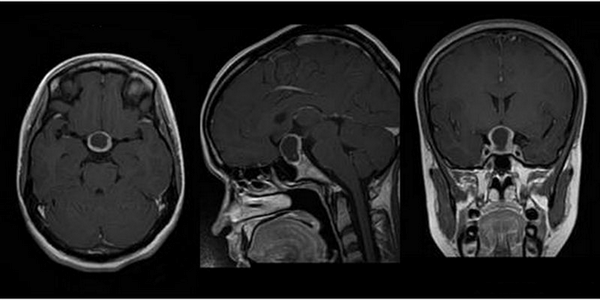

МРТ гипофиза при краниофарингиоме: сканы в разных проекциях